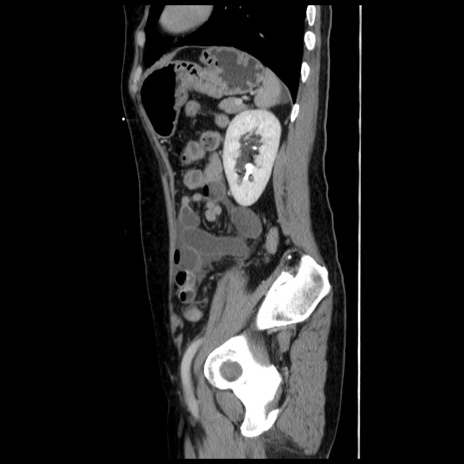

冠状断像